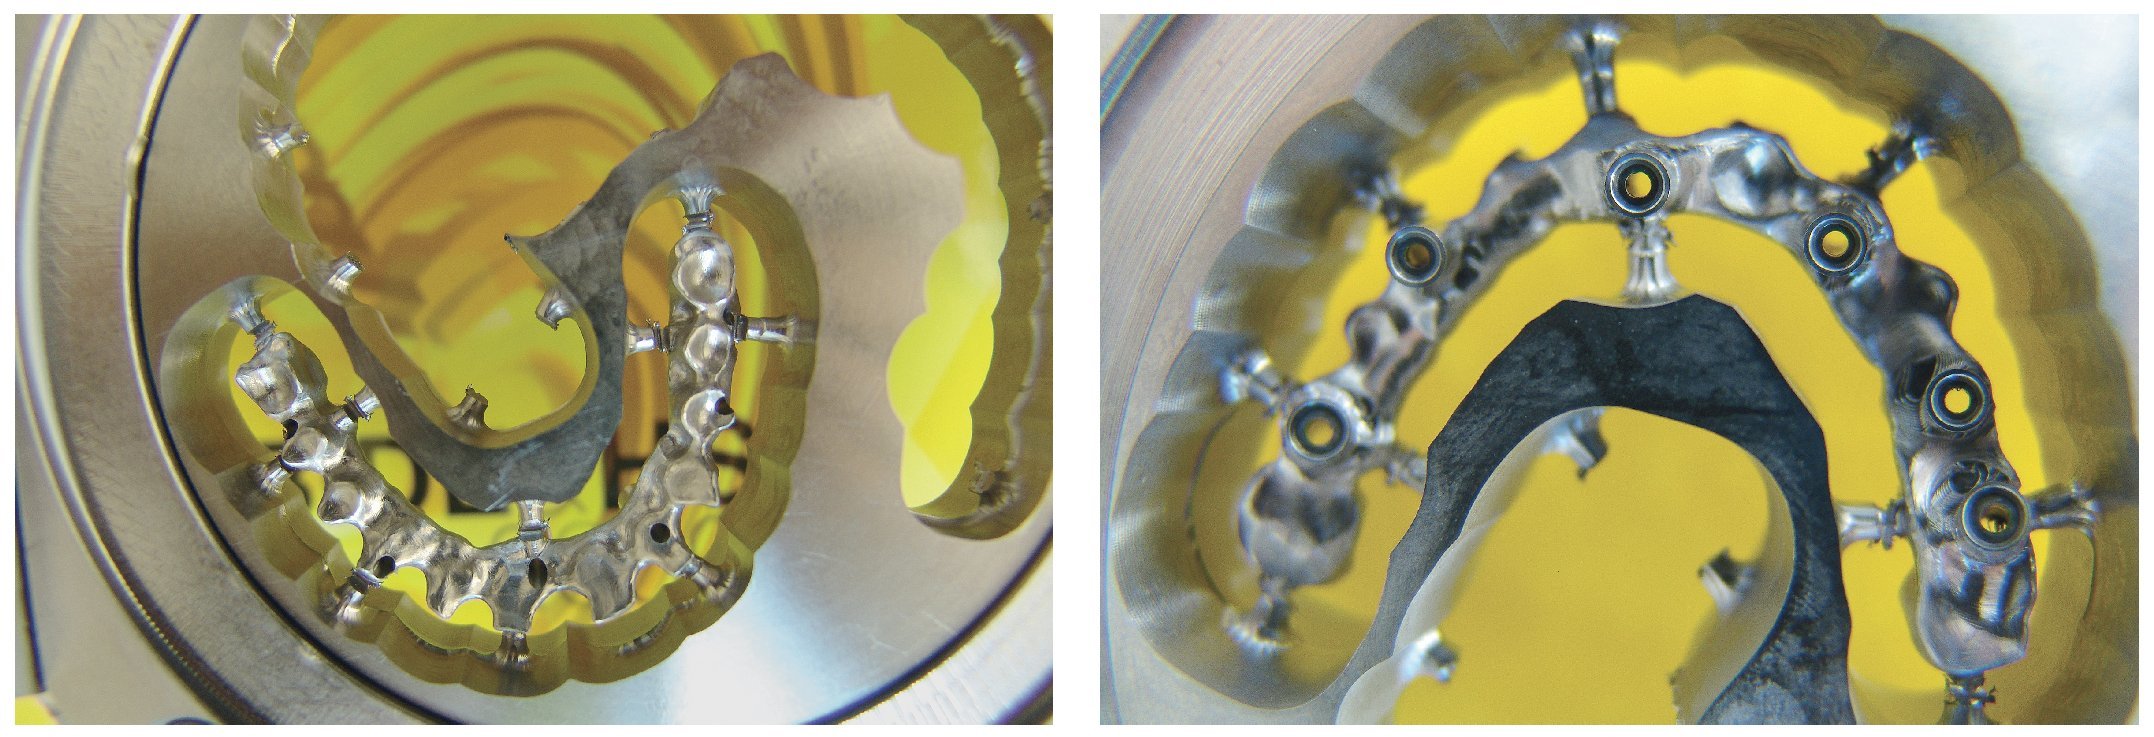

Una vez aprobada la planificación, mediante el software CAD se transmiten los datos en formato STL (Standard Transformation Language o Stereolithography Language) a otro software CAM, el cual procesa nuevamente los datos suministrados para enviarlos en «idioma de máquina» a la fresadora (Zfx, ULTRASONIC 20, Denttec KG-SAS, Gargazon, Italia) encargada de confeccionar la estructura de titanio (figs. 98 y 99). La utilización de fresadoras industriales de cinco ejes para la confección de este tipo de prótesis garantiza un éxito seguro en cuanto a precisión de ajuste y pasivización, y evita casi todos los riesgos que pueden aparecer durante el colado protésico clásico.

Pese a ello, es importante someter las estructuras a un control visual y mecánico, a fin de corregir eventuales discrepancias menores (figs. 99 a 102). A continuación se procede al montaje utilizando dientes protésicos prefabricados de composite (SR Phonares NHC, Ivoclar Vivadent, Ellwangen, Alemania), los cuales reproducen el tipo funcional correspondiente en virtud de sus propiedades morfológicas y estructurales y se integran armoniosamente en cuanto a su longitud dental (figs. 103 a 105). Durante la comprobación de las restauraciones protésicas, se evalúan clínica y radiológicamente ante todo la pasividad y la precisión del ajuste de la estructura. Acto seguido se lleva a cabo una comprobación de la oclusión y de la dimensión vertical, del estado de las prótesis y del tejido blando en la cresta alveolar, así como la verificación del espacio libre lingual, incluida la fonación, y el apoyo de los labios y las mejillas (figs. 106 y 107). También se debe comprobar la facilidad de higiene de la restauración de acuerdo con las habilidades manuales del paciente. A continuación se debe verificar la posición tridimensional de los dientes anteriores con los labios cerrados y durante la sonrisa, así como el aspecto global de la rehabilitación protésica.

Figs. 99 y 100. Confección de la barra de titanio mediante una fresadora de 5 ejes.

Figs. 101 y 102. Vista lateral de las estructuras atornilladas sobre los modelos.